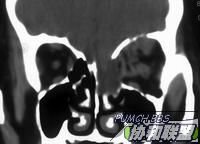

患者女40岁。因左眼角膜溃疡治疗过程中发现左眼球突出,副鼻窦肿瘤来诊。左眼视力0.05,眼部情况如图,角膜溃疡。眼睑轻度肿胀,眼球突出2mm,眼底无法检查。CT和MRI见图

ct

图片点击可在新窗口打开查看